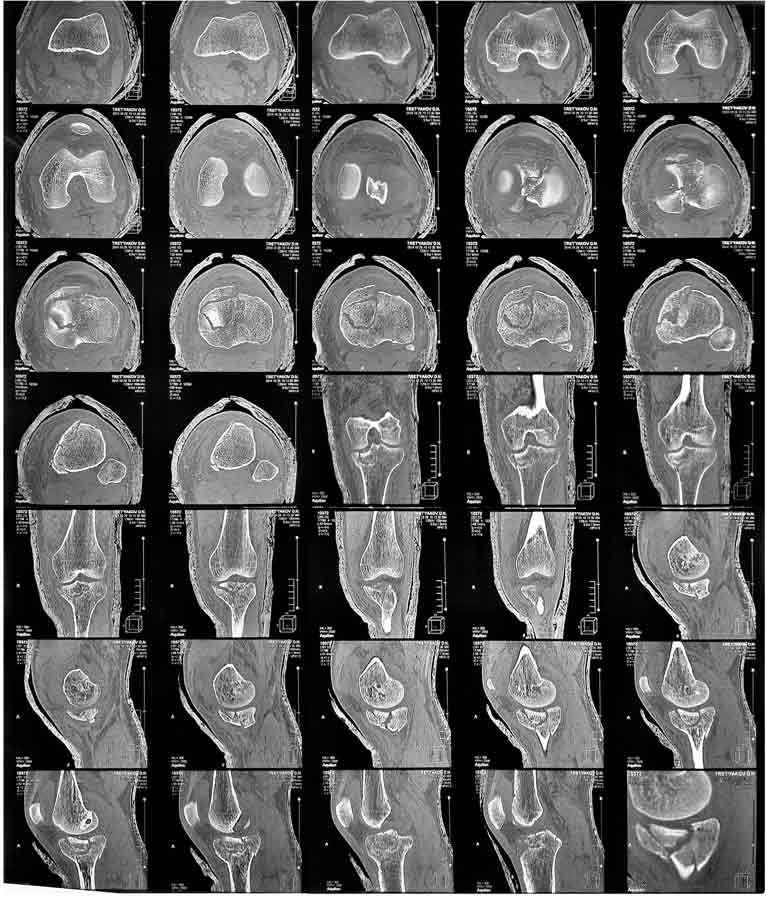

Мужчина, 36 лет, импрессионный перелом медиального (внутреннего) мыщелка

ББК левой ноги.

С его слов обстоятельства травмы: Прыгнул с высоты около 3м и при

приземлении подвернул ногу.

Прилагаю снимки ренген + КТ